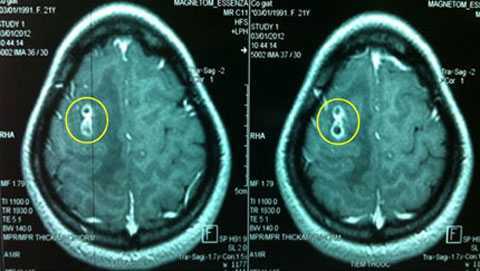

Chị Lan Hương, 25 tuổi (trú tại huyện Tiền Hải, tỉnh Thái Bình) bị tổn thương não nhưng không phải do khối u mà là do giun đũa chó gây nên.